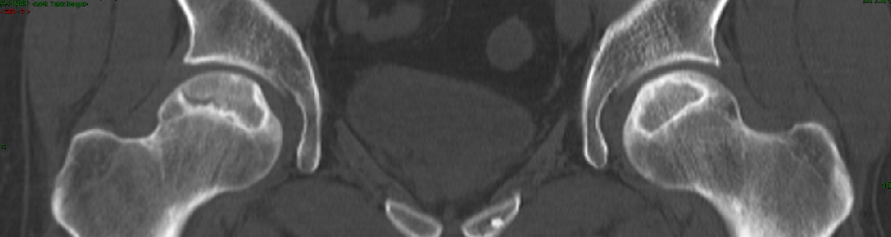

搞定双侧大面积股骨头坏死,原来这么简单!